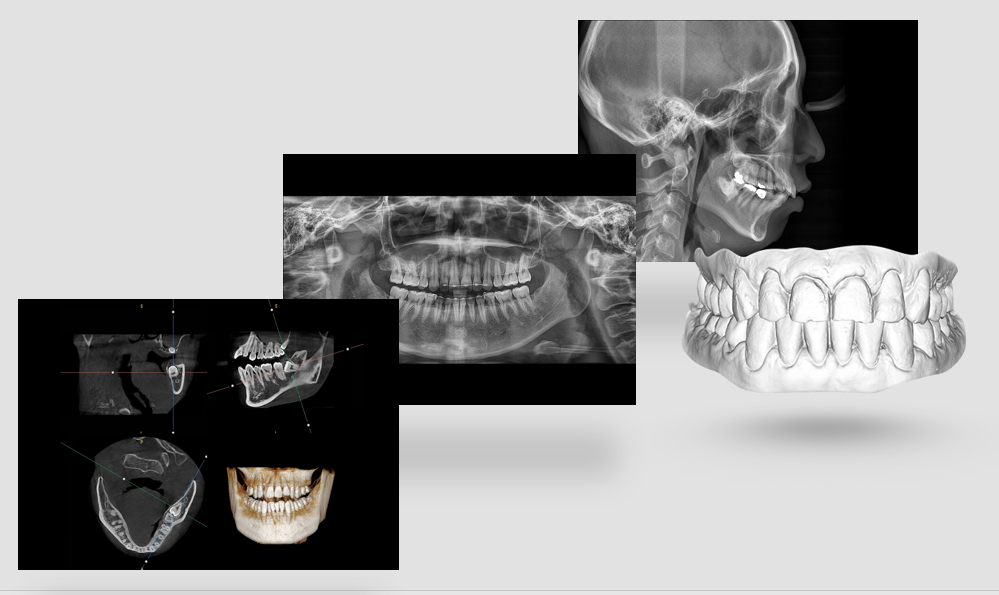

На выставке «Дентал Экспо Красноярск» успешно прошло заседание главных врачей во главе с Садовским Владимиром Викторовичем, Вице-президентом Общества Врачей России, Почетным Президентом СтАР, Директором Национального института исследований и адаптации маркетинговых стратегий (НИИАМС). Помимо насущных вопросов, руководители организаций региона обсудили преимущества и возможности использования стоматологического томографа Genoray Papaya 3D.

Несколько слов про преимущества:

- Уникальный моторизованный подбородочный упор с автоматическим позиционированием головы пациента в зависимости от типа и зоны исследования. Достаточно выбрать зону интереса. Все остальное делает сам аппарат!

18009043640e48e7b4e6074e6c36a5d1.png

- Плоскопанельный детектор имеет самую высокую в классе разрешающую способность

756273e2623420e0e796d77f551404ab.png

- Аппарат можно эксплуатировать в жилых зданиях благодаря соответствию требованиям СанПиН 2.6.1.1192-03 «Гигиенические требования к устройству и эксплуатации рентгеновских кабинетов, аппаратов и проведению рентгенологических исследований», допускающим установку.

ce45767afccd60ae72b13eb9afcc3a8f.png

Приятный бонус для всех участников клуба: рассрочка на 6 месяцев и 5 лет гарантии, в подарок к каждому дентальному томографу идет компьютер.

7fa018f3a1a36ad45a3b839508b4a8bc.png